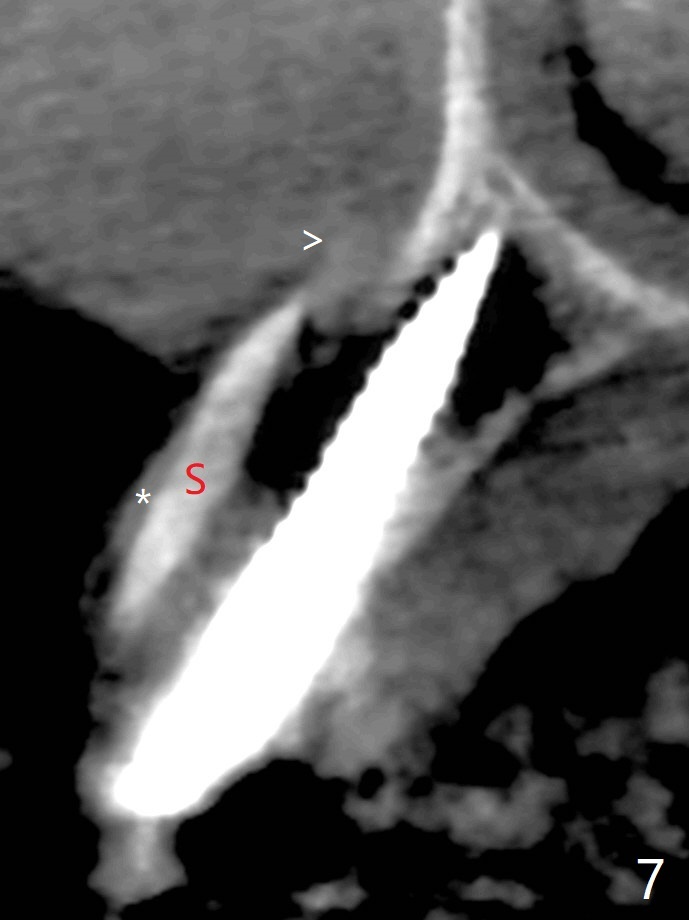

防止拔牙后颊侧骨板萎缩最有效方法是保留部分牙根,例如颊侧(外形象盾牌,简称盾,socket shield (S)),但是制备特别麻烦,尤其是上尖牙。60岁女右上3颊侧骨板隆起(图一至三:*),但是相当狭窄(上下方向),预计强行拔除,势必损失颊侧骨板,造成颊侧塌陷,准备保留盾,如图三红虚线,图六(术后3D长轴断面(十字架:植体))S代表。其实术中试图将整个牙根一起拔除,但是仿佛不行,只好静下心来分根,制备盾,不过困难重重,尤其是除去根尖(防止残余感染),最长外科裂钻似乎达不到根尖,取出后者,颊侧根尖骨板穿孔(图七:箭头)。然后腭侧钻洞(图四),当最后一个钻头保持原位时,在颊侧根尖穿孔处植入粘性骨粉(从牙槽窝口进入,原本粘性骨粉为了修复大面积颊侧缺损用(万一需要强行拔除)),然后才把一段式植体植入(图五),在其余空间填入骨粉,稍微制备基台,制作临时牙冠,最后在牙槽窝开口塞入PRF膜,衬里牙冠,不暂时取出牙冠,衬里相当于临时粘固剂。术后一个月牙根片段和临时牙冠维持良好的牙龈外形(图八,九);术后两个月病人嫌尖牙龈端太尖太长,临时牙冠龈端调整(图十,十一),但愿一个月后龈缘合乎病人期望。